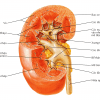

– Cấu tạo thận: xoang thận ở giữa – xung quanh là nhu mô thận (vỏ thận + tủy thận)

+ Xoang thận: chứa mạch máu và thần kinh thận, hệ thống đài bể thận và mô liên kết mỡ. Đài thận nhỏ nhận nước tiểu từ nhú thận, đổ ra đài thận lớn, đài thận lớn hợp thành bể thận – nối với niệu quản.

+ Vỏ thận: nằm ngay dưới bao thận, gồm cột thận (giữa các tháp thận) và các tiểu thùy vỏ từ đáy tháp thận tới bao thận.

+ Tủy thận: do các tháp thận (tháp Malpighi) tạo nên. Đáy tháp thận hướng về phía vỏ thận, đỉnh hướng về phía xoang thận, lồi vào trong xoang thận tạo nên nhú thận – nối với đài thận nhỏ.